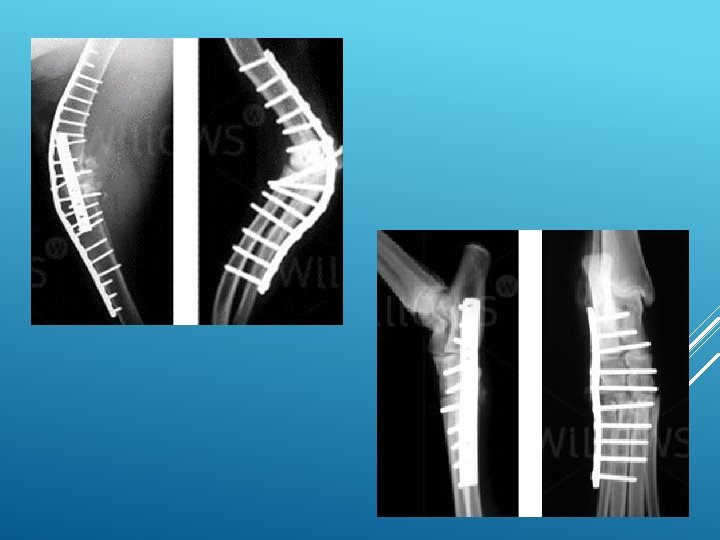

What is arthrodesis? Arthrodesis means the surgical fusion of a joint. In other words, the bones forming the joint are permanently joined together so that there is no movement in this part of the limb. Arthrodesis is a salvage procedure that is generally only performed when there are no other options to save the function of the joint.

What joints can be arthrodesed (fused)? The shoulder, elbow, carpal (wrist), stifle (knee), hock (ankle) and digit (toe) joints can be arthrodesed. The main joint that cannot be fused is the hip joint. This is generally not a problem since the hip joint can be replaced with an artificial one. Elbow and knee replacements are also possible alternatives to arthrodesis of these joints.

There a number of important steps when fusing a joint: the surface of the joint (known as the articular cartilage) must be removed to enable bony fusion. a bone graft should be placed into the spaces between the bones to promote fusion. This may be an autograft (from the patient), an allograft (from a donor) or a combination of both.